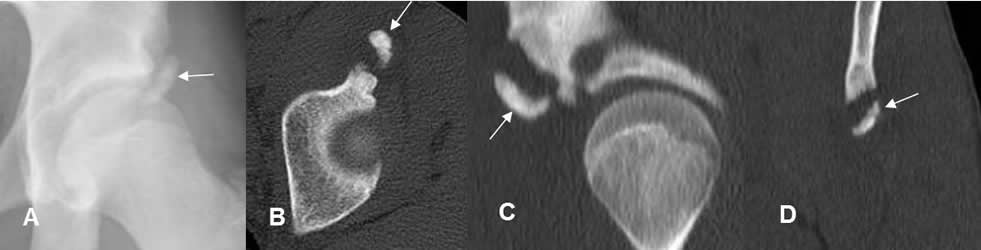

Fig 52 A. Avulsión.

A: Rx AP, B: TAC axial, C: TAC reconstrucción sagital y D: TAC reconstrucción coronal. Fragmento en relación con la espina tibial anterior inferior, que corresponde a avulsión.